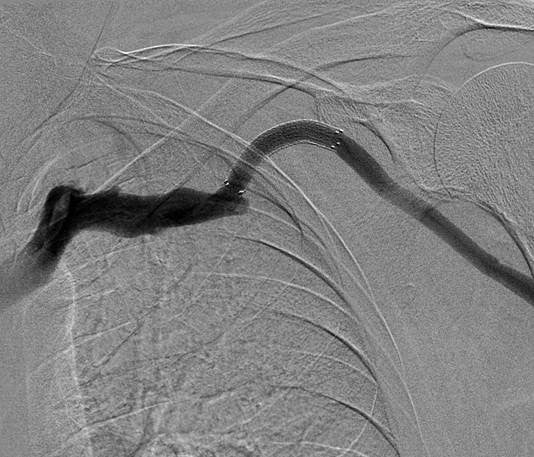

Direct left brachiocephalic fistula access. Venography demonstrated recurrent cephalic arch stenosis. Venoplasty to 7 mm with a high-pressure balloon and recoil stenosis. Upsizing of sheath access. Deployment of a 7 mm x 5 cm GORE® VIABAHN® Device, and post-dilatation.

- Symptomatic and recoil cephalic arch stenosis requires a durable solution to restore and maintain patency

- When venoplasty fails the GORE® VIABAHN® Device offers a durable solution as it conforms very well to the anatomical configuration of the arch without kinking